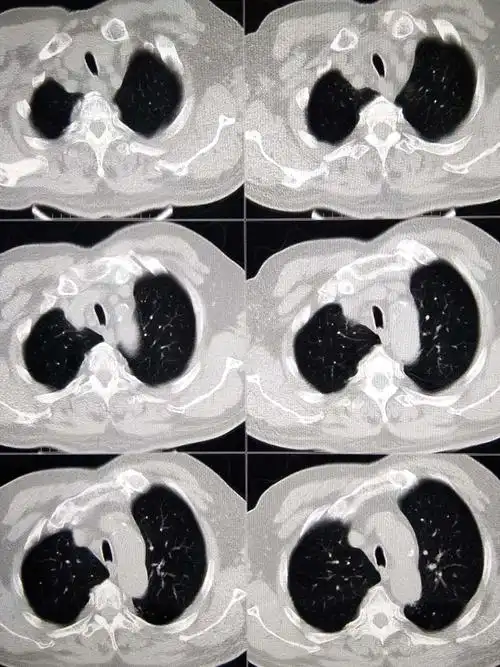

早期肺癌ct图

世界肺癌日:一起关注如何发现早期肺癌